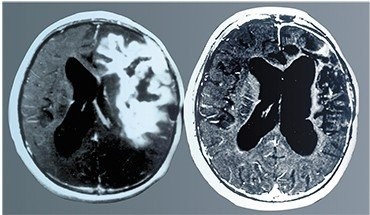

Один из самых поразительных случаев излечения рака с помощью вирусной терапии связан с глиобластомой, опасной и быстро развивающейся опухолью головного мозга. У больного (пятнадцатилетнего подростка) опухоль была уже очень большой и обычная терапия была бесполезна. Лечение проводилось вирусом болезни Ньюкасла. Вверху – томограммы мозга больного до и после лечения. По: (Csatary and Bakacs, 1999)